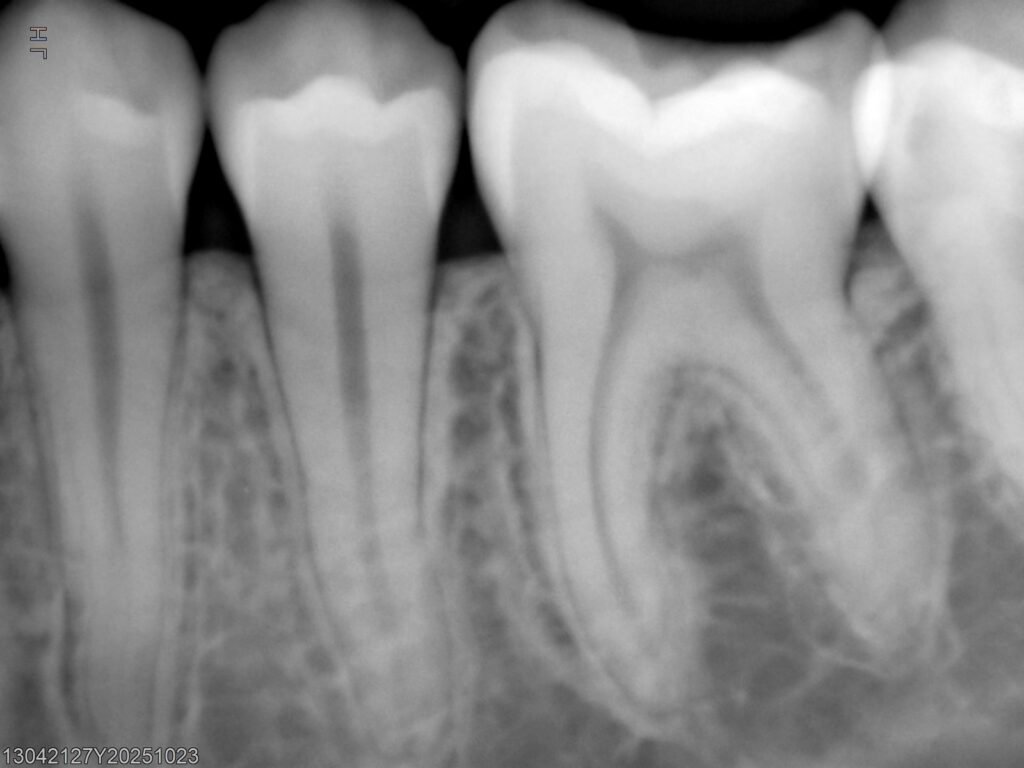

• Radiografías digitales

• Medición de bolsas periodontales